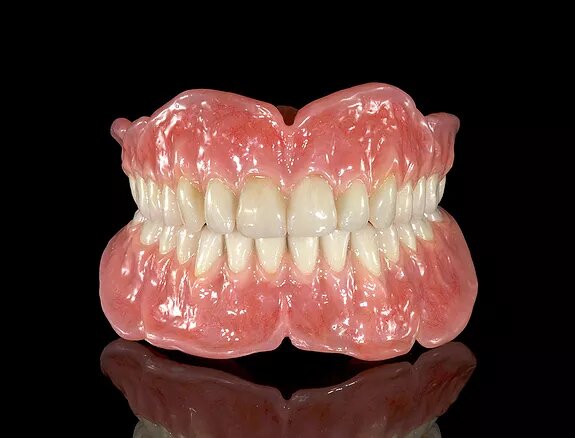

MOBILNA PROTETIKA

• Potpune i djelomične akrilatne proteze